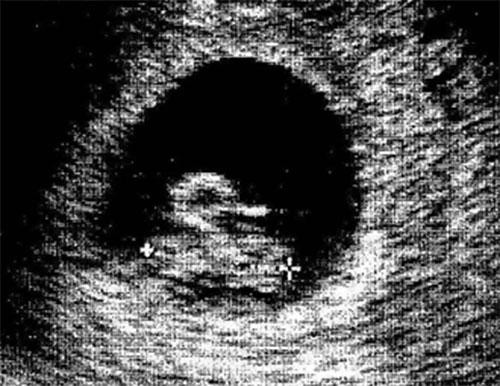

Şimdi de ultrasonda bebek yerine bir ördek gördüğünüzü düşünün. Merak etmeyin, aslında sadece “pareidolia” sendromunu yaşıyorsunuz.

Yani gördüğünüz alelade şekilleri anlamlandırmaya çalışma hali…

İşte bebek ultrasonlarında çekilen ve bazı anne babalara mini kalp krizi geçirten bebek fotoğrafları!